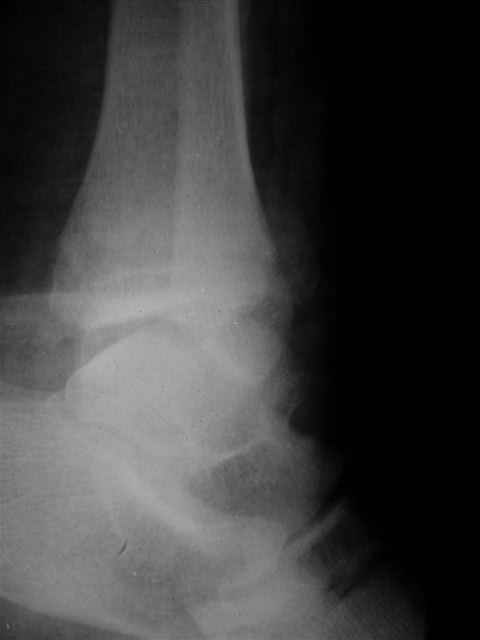

Уважаемый Иван,

Я предупреждал, что ничего сверхъестественного. Каюсь, что одна из спиц прошла несколько дальше, чем нужно было, но главное - перелом стабилизирован и больной работает суставом в полном объёме, несмотря на представленную раннее травму коленного сустава.

Всего вам Доброго,

Евгений И Чекашкин